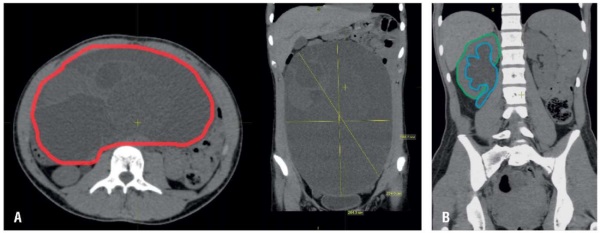

Aim: to present a clinical case of a teenage girl with giant ovarian cystadenoma complicated by hydronephrosis due to ureteral compression.

Case presentation. A female patient R., 17 years old, was admitted to the surgical department on 12.02.2025, with complaints of abdominal enlargement, abdominal pain lasting over 4 months, frequent urinal miction and algodismenorrhea. Medical history dated of January 2025 showed that imaging research methods performed in different organizations revealed a multilocular cyst of the abdominal cavity – a mucinous cystadenoma of the left ovary, sized 193×195×271 mm, complicated by hydronephrosis of the right kidney. Physical examination revealed a local abdominal pain in the umbilical region as well as increased abdominal volume. General blood test found signs of mild iron deficiency. Blood screening tests for serum alpha-fetoprotein (AFP), human chorionic gonadotropin (hCG) and cancer antigen-125 (CA-125) levels allowed to exclude oncological pathology.

Results. Further surgical treatment was performed. On 17.02.2025, patient R. underwent laparoscopic cystectomy. The passage of urine quickly returned to normal after removal of obstruction cause. A follow-up ultrasound examination on the day 7 post-surgery showed that the pelvis of the right kidney was markedly decreased. The postoperative period was unremarkable. Patient R. was discharged on day 8 with improvement. Recommendations were provided.